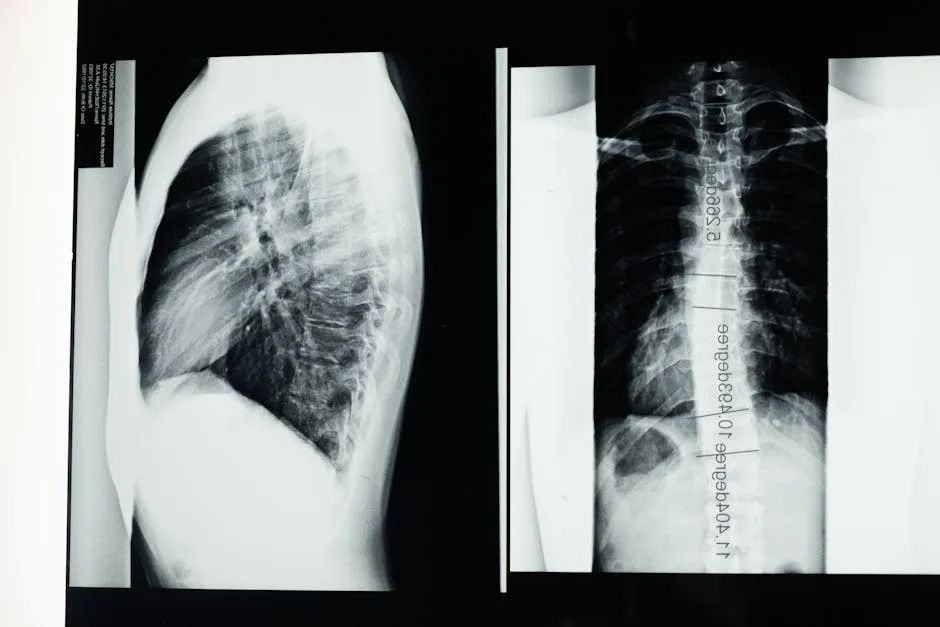

①腰椎X线片:判断腰椎有无骨质增生和侧突、腰椎前突是否存在、侧方是否有滑移、腰椎矢状面或侧方滑脱。

图片来源于Pexels